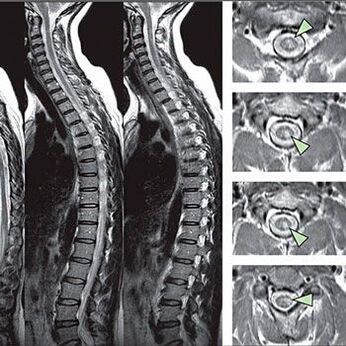

A mellkasi gerinc osteochondrosis diagnosztizálására szolgáló módszerek

A világos diagnózis érdekében a szakembernek figyelembe kell vennie a beteg panaszait. A nőkben a következő tünetek és érzések lehetővé teszik az emlő osteochondrosis kimutatását: Ha a mellkas bizonyos pontjaira nyomják, súlyos fájdalom szindróma jelenik meg.

Az érzékenységi rendellenességek jeleinek azonosítása érdekében speciális funkcionális teszteket végeznek. Az instrumentális módszerekből származó diagnózis leginformatívabb lehetősége az x -tray teljesítménye. A gerinc alapos vizsgálatához azonban gyakran elvégzik az MRI -t és a CT -t. A szív- és érrendszeri betegségek gyanúja esetén a betegnek ajánlott az EKG -eljárás során.